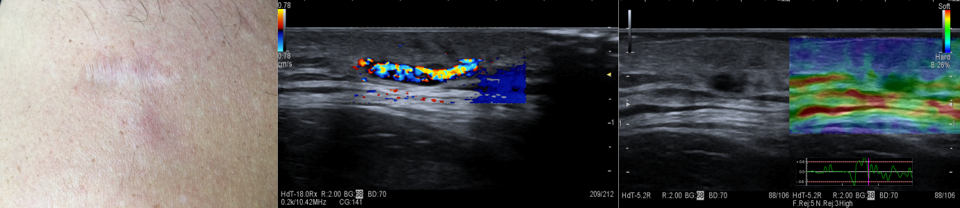

4. LINFOMI CUTANEI

Recidiva linfoma B cutaneo: all’ecografia aumento dello spessore dermo-epidermico e marcata vacolarizzazione. Componente Hard all’esame elastosonografico.